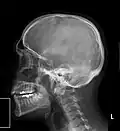

Zdjęcie boczne głowy i szyi

Zdjęcie boczne czaszki – widoczny oponiak